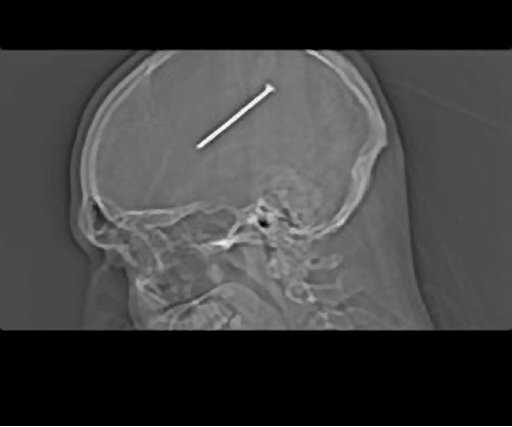

OAK LAWN, Ill. (AP) — Gail Glaenzer still can't believe that her fiancé unknowingly shot a nail into his skull, let alone that he posted a picture of the X-ray on Facebook during his ambulance ride between hospitals for surgery.

But she was joking about the circumstances Friday, a day after doctors successfully removed the 3 ¼-inch nail from Dante Autullo's brain.